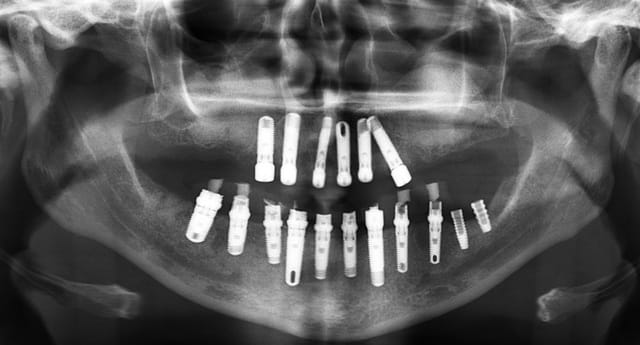

Maintenant voilà un cas réalisé(ressemblant au tien je pense); avec la pano avant et la pano à trois mois! La patiente est ressortie du cabinet 5 heures après avec ses dents. J'ai fait refaire un scan à la patiente pour avoir la position des implants et faire la comparaison entre la planif et le travail executé.

Je vais entendre hurler pxav car les implants ont été mis en distraction osseuse je dirai plutot en condensation... bref. A vous de voir!